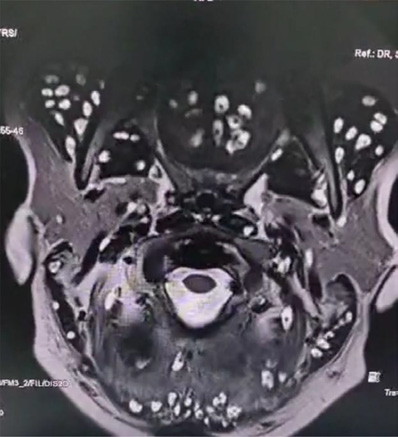

Magnetic Resonance Imaging (MRI) of the brain demonstrated multiple well-defined ring-enhancing lesions with eccentric mural nodules representing the scolex in the bilateral cerebral and cerebellar hemispheres, accompanied by surrounding edema – which are findings highly suggestive of neurocysticercosis (Figure 1) [4].

In addition, multiple cystic lesions were observed within the extraocular, facial, and tongue muscles, each containing an eccentric scolex, consistent with disseminated myocysticercosis (Figures 2 and 3). These lesions exhibited hyperintense signals on T2-weighted and hypointense signals on T1-weighted sequences, confirming their parasitic nature.

Explanation: On MRI, neurocysticercosis is identified by multiple ring-shaped lesions, each showing an eccentric nodule representing the scolex. These lesions are often accompanied by perilesional edema. In this case, their presence in the cerebral and cerebellar hemispheres provided a clear and definitive diagnosis.

Explanation: Muscular involvement was detected through MRI, which revealed multiple cystic lesions within the extraocular, facial, and tongue muscles. The presence of an eccentric scolex inside these lesions confirmed that they were parasitic in origin, indicating disseminated myocysticercosis, which is an uncommon but clinically relevant finding.